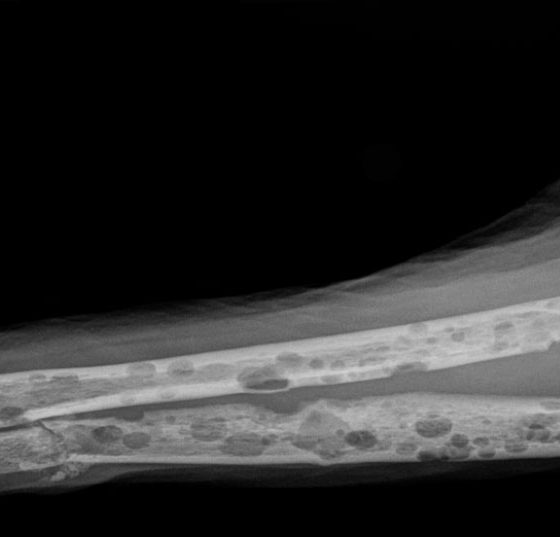

• Multiples Myelom

Noch immer gilt das Multiple Myelom, die pathologische Vermehrung von Immunglobulinen im Knochenmark, als unheilbar. Hochwirksame Medikamente verlängern jedoch die Überlebenszeit – in seltenen Fällen auf bis zu 20 Jahre....…